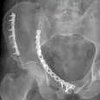

Удаление металлоконструкции из таза

Удаление металла из бассейна. Программируемая операция, при которой травматолог удаляет металлические имплантаты, ранее использовавшиеся для фиксации отломков при переломах таза. Это редко выполняется из-за высокой инвазивности вмешательства. Проводится только при наличии серьезных показаний: нагноения на уровне фиксатора, аллергических реакций на компоненты металла, нестабильности перелома при отсутствии признаков разрушения отломков Он проводится под общим наркозом в травматологическом стационаре.

В большинстве случаев удаление металлических структур из таза сопровождается обширным повреждением структур мягких тканей или высоким риском повреждения жизненно важных анатомических структур, поэтому удаление имплантатов тазовой фиксации выполняется только тогда, когда они настоящие абсолютные показания. Исключением является операция по удалению фиксаторов из лобкового симфиза, которая может быть выполнена без значительного повреждения мягких тканей. Показанием для извлечения металлической структуры является нестабильность фиксации в сочетании с глубокой инфекцией или недопустимым переломом, индивидуальная аллергическая реакция на металл, из которого сделан имплантат, высокая вероятность развития заболевания или осложнения, вызванные структурой металла. Во всех других случаях травматологии имплантаты обычно не удаляются из таза.